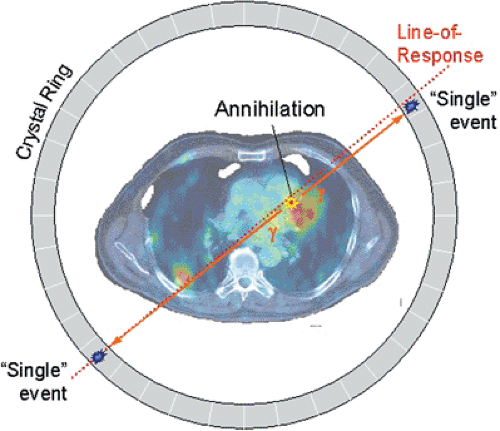

What is the relationship between each detector pair inside the ring of detectors in a PET camera?

Each detector works together with the detector opposite to it – allows it to pick up on a line of response

What is a line of response?

When the photons from an annihilation reaction are emitted, they will travel in opposite directions of one another – makes a 180-degree line almost

How does a ‘dot’ from our image translate from the reaction at the PET detectors?

The detectors create a dot on our scanned image from the point at which the 2 photons are overlapping – or where they cross each other in the ring of detectors but we still need more information to specifically determine it!

What is needed in order for the PET detectors to determine where an annihilation reaction occurred on a line of response?

Requires multiple line of responses to figure out where the intersection of where the annihilation reaction took place

Is a line of response able to determine where the photon originated from?

No, it’s only able to determine where the annihilation took place